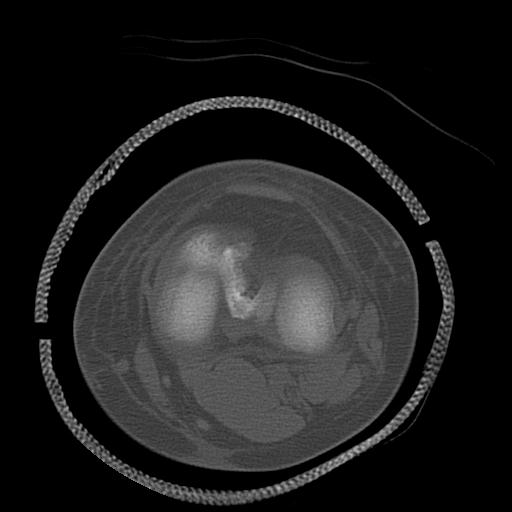

49554 3/13 膝 4R 3/16 4R 1/18 2R 78歳男性 膝蓋骨骨折